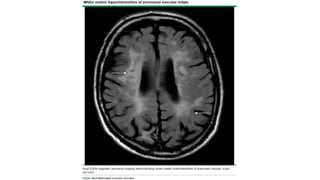

EVALUACIÓN

• Pequeñas áreas

redondeadas (<10 mm) de

pérdida de señal

(hipointensidad) áreas

depósito hemosiderina.

Microsangrados:

• Hipointensidad lineal a lo

largo de superficie cortical.

• A lo largo circunvolución

supratentorial simple o

múltiple→ gral/ Sg AAC,

otras causas hemorragia

superficial (Malform

vasculares o trombosis

venosa cortical).

Siderosis

superficial:

• Gral/ no se informan en

práctica radiológica de

rutina. Se vuelven más

visibles en pctes con enf

cerebrales de pequeños

vasos.

• Atrofia: atrofia cerebral

acelerada.

Espacios

perivasculares:

Eric B Larson. Evaluation of cognitive impairment and dementia. ©2020 UpToDate, review April 2020.